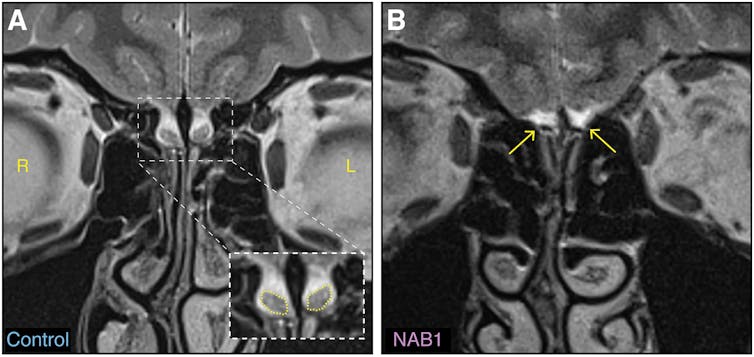

While looking at the MRI brain scan of a 29-year-old woman that had been taken for a different study, researchers in Israel recently stumbled upon a scientific mystery. The woman appears to have no olfactory bulbs.

People like me and most of you have two of these bulbs: they sit right above your nasal cavities, snuggled up against the bottom of your brain. They’re small but important little processing boxes: the nerves in your nose that pick up scents around you feed into these bulbs.

All of these delicate components work together, granting you the sense of smell! Some brains do have damaged olfactory bulbs or none at all: this is sometimes seen in people with anosmia, an inability to smell.

But back to our 29-year-old woman who appears to lack olfactory bulbs. It turns out her sense of smell is perfectly fine. So what’s going on here?

As the 29-year-old woman was also left-handed, they started scanning other left-handed and similarly aged women. It only took nine such scans to discover another person without apparent olfactory bulbs, but a good sense of smell. The plot thickens!

Among the experiments, a massive open data set of very high quality was also checked: of 1,113 people (606 women), three others were found without apparent olfactory bulbs, but with the sense of smell. None were men. One was left-handed.